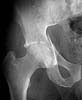

The iliac oblique reveals a displaced fracture of the posterior column, and it appears that the femoral head is not congruous with the acetabulum.

AP, obturator oblique films and a CT scan will better reveal the extent of the injury.

> The iliac oblique reveals a displaced fracture of the posterior column,

IMHO, it' s a transverse fr.

He has fractured right acetabulum. Patient was fully conscious, adequate, pelvic examination left no suspicion of pelvic trauma. How to explain that he walked 2 weeks with no symptoms?